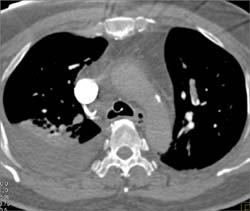

Pulmonary Embolism